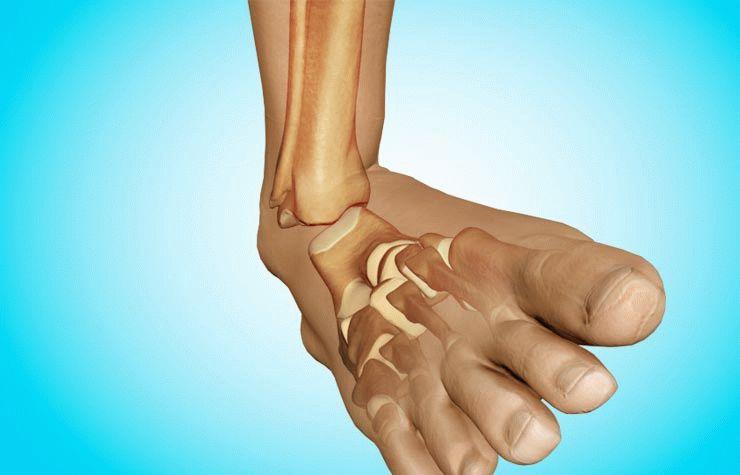

Травматический вывих – это повреждение ноги, которое сопровождается ее деформацией в зоне поврежденного сустава. Также появляется синяк, гематома, интенсивная боль и нарушение двигательных функций. Если при вывихе суставы полностью престают соприкасаться, то это полный вывих. Подвывих (то есть частичный подвывих) характеризуется частичным соприкосновением суставов.

При любом вывихе происходит разрыв капсулы сустава, через который и выходит суставная жидкость. При сильной травме наблюдается разрыв сухожилий, кровоизлияние в окружающие мягкие ткани. Если вовремя не оказать помощь, возникнут осложнения и последствия. Распространенным считается вывих подколенника и стопы – двадцать пять процентов случаев от всего количества вывихов. Вывих бедра встречается в пяти процентах случаев.